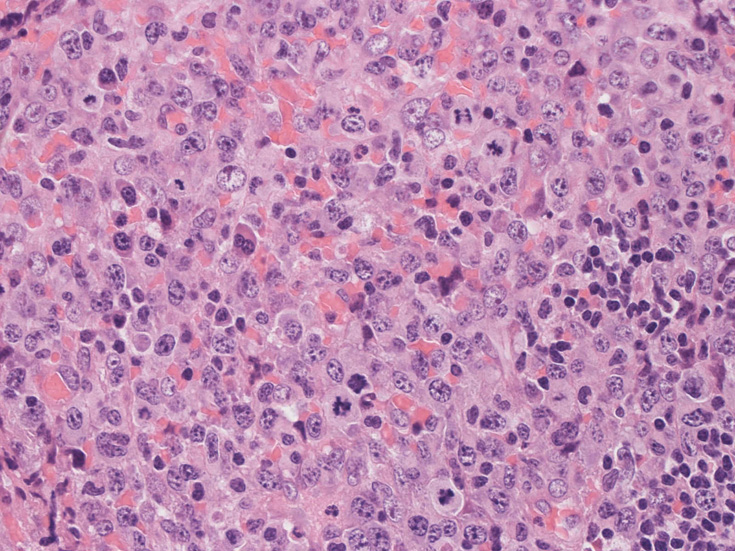

リンパ節, 増殖腫瘍細胞の病理所見

腹膜脂肪組織内から生検されたリンパ節は基本構造を失っている。低倍率のHE所見では異型細胞が不鮮明な結節構造を形成して増殖している。一次リンパ濾胞を腫瘍細胞が置換しているように見える所見がある。

高倍率x400では, 増殖細胞はcentroblastに似て複数の明瞭な核小体をもった淡明な大型類円ないし卵円形核を持っている。核分裂像が多い。この症例では多型はめだたない。典型的な腎臓型のくびれた核を持つ細胞などはない。ALKの形態的variant症例と考えられるが, 化学療法後の再発による影響も否定できない。